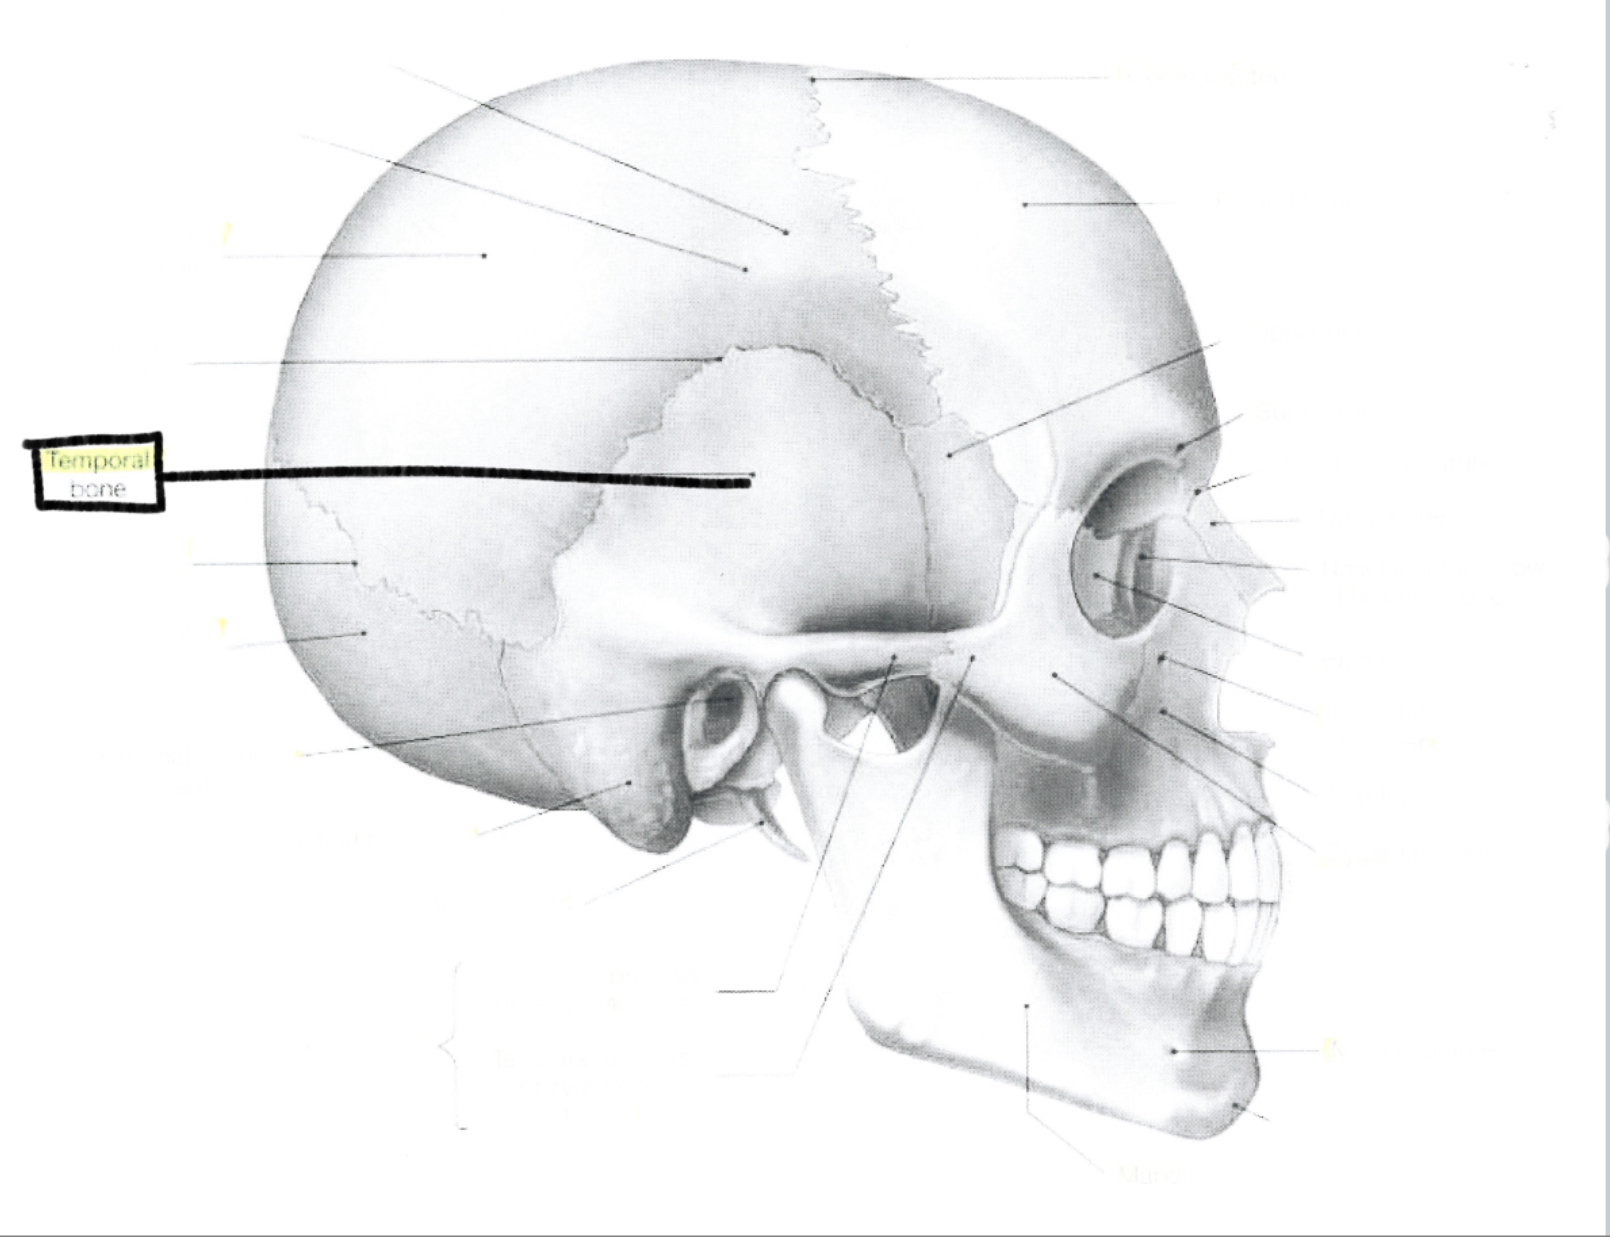

What is this?

Temporal bone